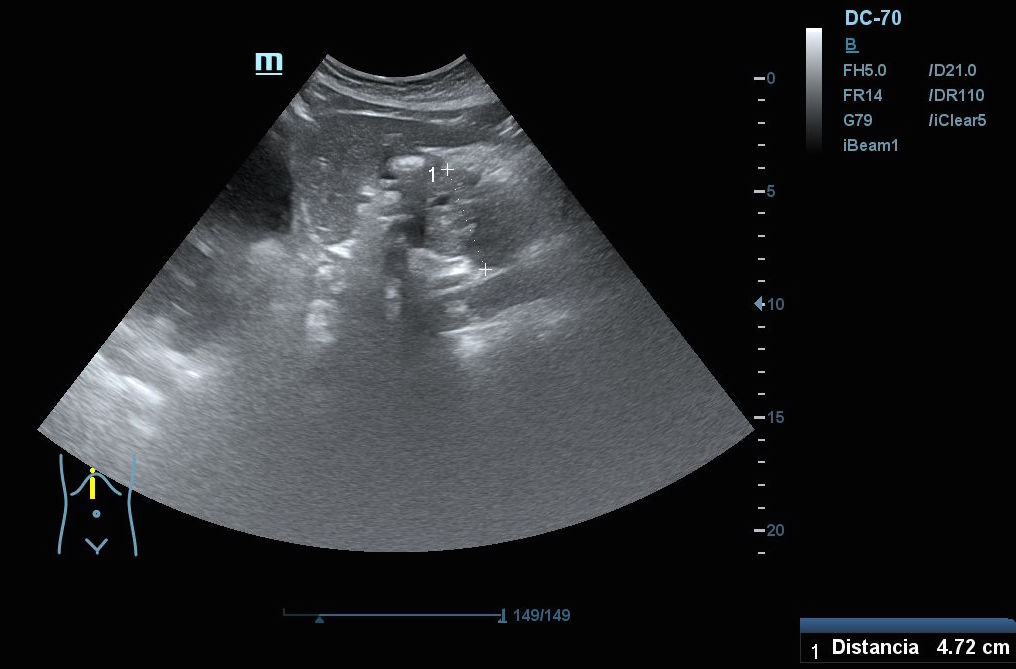

Hallazgos ecográficos: En el epigastrio se observa una imagen anecoica tubular, sin captación en Doppler, con un diámetro mayor a 2 cm, que sugiere una dilatación del colédoco (imagen 1). La vesícula biliar se encuentra completamente distendida y hepatizada, con una imagen en «doble cañón de escopeta» sugestiva de colestasis (imagen 2). En los cortes longitudinales se identifica una masa anterior a la aorta en el corte paramedial izquierdo, aparentemente localizada en el cuerpo del páncreas (imagen 3). En los cortes transversales se observa una masa que afecta tanto al cuerpo como a la cabeza del páncreas (imagen 4).

En la resonancia magnética se confirma la presencia de una masa en la cabeza y el cuerpo del páncreas. También se observa dilatación de la vía biliar intrahepática y extrahepática e invasión de los vasos mesentéricos superiores, la vena porta y la arteria hepática.

Mediante colangiopancreatografía retrógrada endoscópica (CPRE), se realiza una biopsia que confirma la presencia de un adenocarcinoma pancreático.